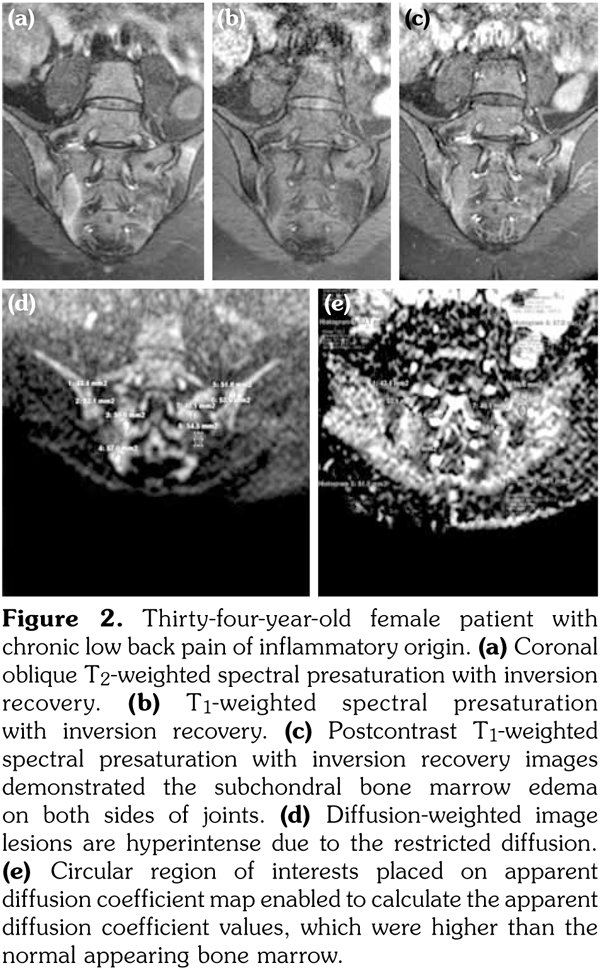

All patients underwent MRI at 1.5-Tesla superconducting eight channel MRI system (Achieva, Philips Medical Systems, Best, The Netherlands) provided with high-speed gradients. The following sequences of sacroiliac joints in the oblique coronal and axial planes as the standard protocol were obtained in the supine positions with a high-resolution phased-array coil: turbo spin-echo T1-weighted (repetition time/echo time, 600/minimum), turbo spin-echo T2-weighted (repetition time/echo time, 2100/80), T2-weighted spectral presaturation with inversion recovery (SPIR) (3100/70), T1-weighted SPIR (600/ minimum) with and without gadolinium-based contrast agents (0.1 mmoL/kg of body weight). All sequences contained lower lumbar spine (Figures 1a-c).

Diffusion-weighted imaging was performed by single-shot spin-echo echo-planar imaging technique with diffusion gradient b values of 0 and 600 s/mm2 (Figure 1d). The following DWI parameters were used: field of view: 25 (right-left) x 32 (anteroposterior) cm; number of excitations: 2; matrix size: 176x176; slice thickness: 4 mm; repetition time/echo time, 8000/minimum; intersection gap: none.

Sacroiliac joints were assessed according to ankylosing spondylitis criteria. Before evaluation of standard MRI protocol, patients’ information was removed from images. Afterwards, two experienced radiologists evaluated the images for the presence of inflammatory activity twice at separate sessions to assess interobserver variability. Following the examination of T2-weighted SPIR, contrast- enhanced T1-weighted SPIR, and DWIs at b values of 600 s/mm2, two radiologists and rheumatologists reached a consensus on the disease activity in the light of positive features of Berlin criteria. The DWIs were transferred to a separate workstation (Phillips, Extended MR workspace, 2.6.3.2.HF3, Netherlands). ADC maps were generated. T2-weighted SPIR images, contrast-enhanced images and diffusion-weighted images with ADC maps were put on the screen side by side. In the disease group, the hyperintense lesions on T2-weighted SPIR images and enhanced focuses on contrast- enhanced images were noted and the same lesions were marked on DWI images and ADC map. A circular ROI with a range of 40-75 mm2 was placed in those areas. In the control group a circular ROI was placed in the subarticular area of joints. Also, the same process was performed for the normal-appearing bone marrow areas near the joints of the disease group (Figure 2). Four standard measurements were conducted from each joint, including two on sacral and the other two on the iliac side for all patients (Figure 3). Additionally, two measurements were conducted from the fifth lumbar vertebra and one from each iliac wing (Figure 4). All measurements were performed twice. ADC values were expressed as square millimeters per second. The r-ADC ratio was calculated by dividing ADC value of subchondral bone or inflammatory lesions to ADC values of the fifth lumbar vertebra and iliac wings.